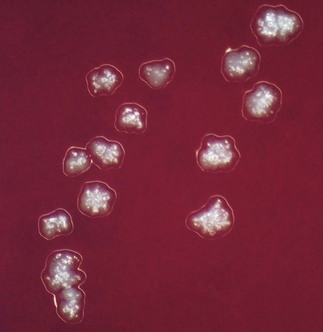

Grows slowly under anaerobic conditions, on blood or serum glucose agar at 37°C. After about a week, it appears as small, creamy-white, adherent colonies on blood agar. The colonies resemble breadcrumbs or the surface of ‘molar’ teeth (Fig. 13.1). Because of the exacting growth requirements and the relatively slow growth, isolating this organism from clinical specimens is difficult, particularly because the other, faster-growing bacteria in pus specimens tend to obscure the slow-growing actinomycetes. ‘Sulphur granules’ in lesions are a clue to their presence. When possible, these granules should be crushed, Gram-stained and observed for Gram-positive, branching filaments, and also cultured in preference to pus.

Fig. 13.1 Molar tooth-shaped colonies of Actinomyces israelii on blood agar.